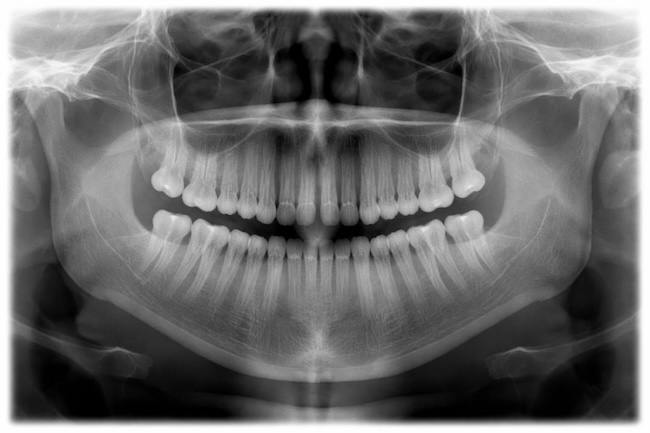

Rontgen gigi merupakan prosedur yang umum dilakukan untuk menunjang perawatan gigi (seperti diagnosis karies dan penyakit periodontal) dan mengevaluasi gangguan perkembangan serta pertumbuhan gigi. Akan tetapi, rontgen gigi tidak terlepas dari efek samping terhadap kesehatan pasien.

Dalam konteks Indonesia, hasil studi ini sangat relevan sebagai peringatan akademik dan kebijakan. Praktik radiologi dental (seperti periapikal, panoramik, dan penggunaan cone beam computed tomography) semakin meningkat dan sering kali dilakukan tanpa pedoman berbasis risiko individual yang ketat, khususnya pada anak dan remaja.